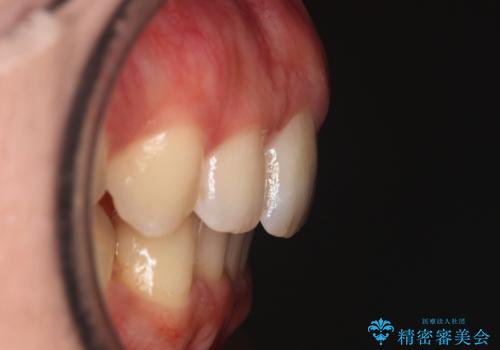

右側臼歯部の咬合改善のために、臼歯部のみ部分的なワイヤー矯正を行い、咬合改善がみられてからインビザラインにて全体的な矯正を行なっていく治療計画を立てました。

噛み合わせをよくするために、ワイヤー矯正とインビザライン矯正のどちらの期間も必要な箇所にゴム掛けを行いながら治療を行いました。